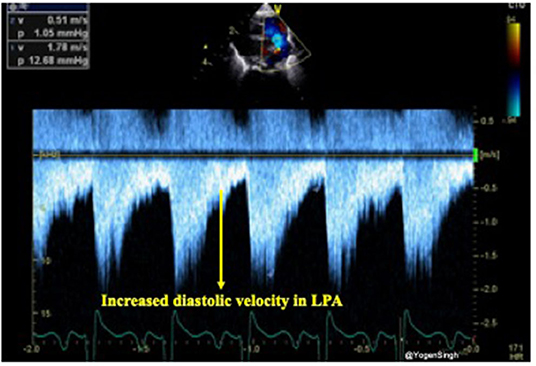

The presence of forward pulmonary flow in diastole in the left pulmonary artery (LPA) has been described as a sign of significant left to right shunt through the PDA. Using pulsed wave Doppler in the LPA mean and end-diastolic velocity can be measured and cut-off points of 0.42 and 0.20 m/s, respectively, have been described as indicative of significant ductal shunt (24) (Figure 8).

Figure 8. Doppler assessment of blood flow in left pulmonary artery (LPA) showing increased diastolic velocity indicative of significant ductal shunt in diastole leading to turbulence and increased velocity.